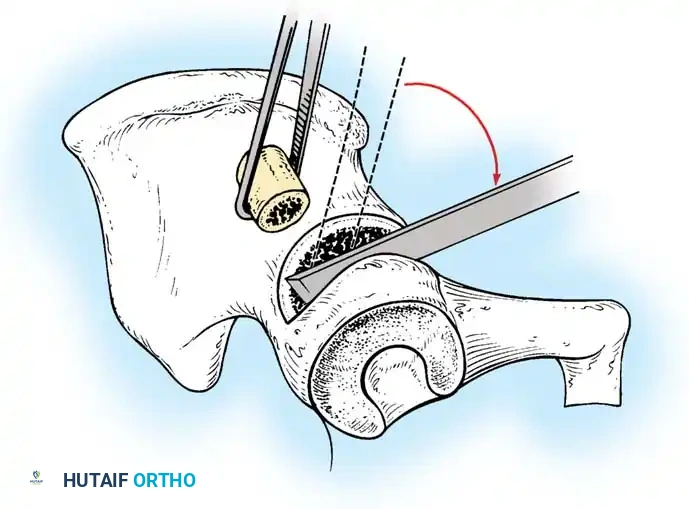

Intraoperative view of the anterior approach to the hip, demonstrating capsulotomy and exposure of the dysplastic joint.

Anterior Approach (Smith-Petersen):

1. Incision: "Bikini" incision below the iliac crest.

2. Interval: Develop the plane between the tensor fasciae latae (superior gluteal nerve) and the sartorius (femoral nerve).

3. Deep Dissection: Detach the rectus femoris from the AIIS. Isolate and release the iliopsoas tendon at the pelvic brim to relieve the hourglass constriction of the capsule.

4. Capsulotomy: A T-shaped or I-shaped capsulotomy is performed parallel to the acetabular margin.

5. Joint Clearance: Excise the ligamentum teres, clear the pulvinar, and incise the transverse acetabular ligament inferiorly. Never excise the limbus, as it is critical for future acetabular growth; radial incisions may be made if it is severely inverted.

6. Capsulorrhaphy: Following concentric reduction, the redundant capsule is advanced superiorly and laterally to stabilize the joint.